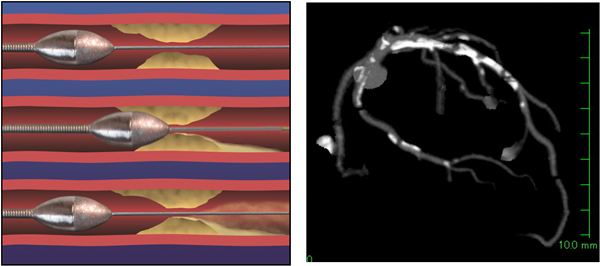

狭心症の症状は階段を昇った際や重い荷物を持った時などに胸が苦しくなる、冷や汗を伴う息切れなどが代表的であり、当院の外来では次の精密検査として患者さんへの負担の少ない心臓CTや心筋シンチグラムなどで通常確認を行います。但し心電図や血液検査、問診などの結果心筋梗塞に移行しかけている不安定な状態といった危険な兆候があれば患者様と充分相談のうえ心臓カテーテル検査を優先する場合もあります。

負荷心筋シンチ画像 心臓CT画像(赤丸部分 狭さく)

心臓CTボリュームレンダリング画像